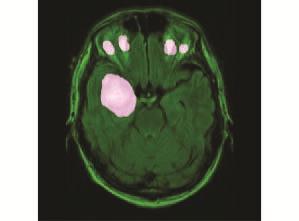

(a)Glioma(b)Pituitary(c)Meningioma(d)Normal

Fig.4. Sampleofimagesfromeachclassofbraintumours generatedfromtheMRI.